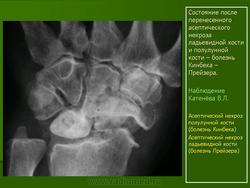

Остеохондропатия. Прейзера болезнь. Паннера болезнь. +

Прейзера болезнь (m,Preiser), остеохондропатия ладьевидной кости кисти, остеомаляция ладьевидной кости, остеохондрит ладьевидной кости. Описана немецким ортопедом Preiser G. К. в  1911 г. Относится к группе остеохондропатий. Клинически проявляется болью, ограничением движений в лучезапястном суставе, боль усиливается при сжатии пальцев в кулак. Рентгенологически определяется уплотнение ладьевидной кости, неравномерность ее структуры, наличие мелких кист. Эти изменения иногда напоминают картину перестройки ладьевидной кости после ее перелома.